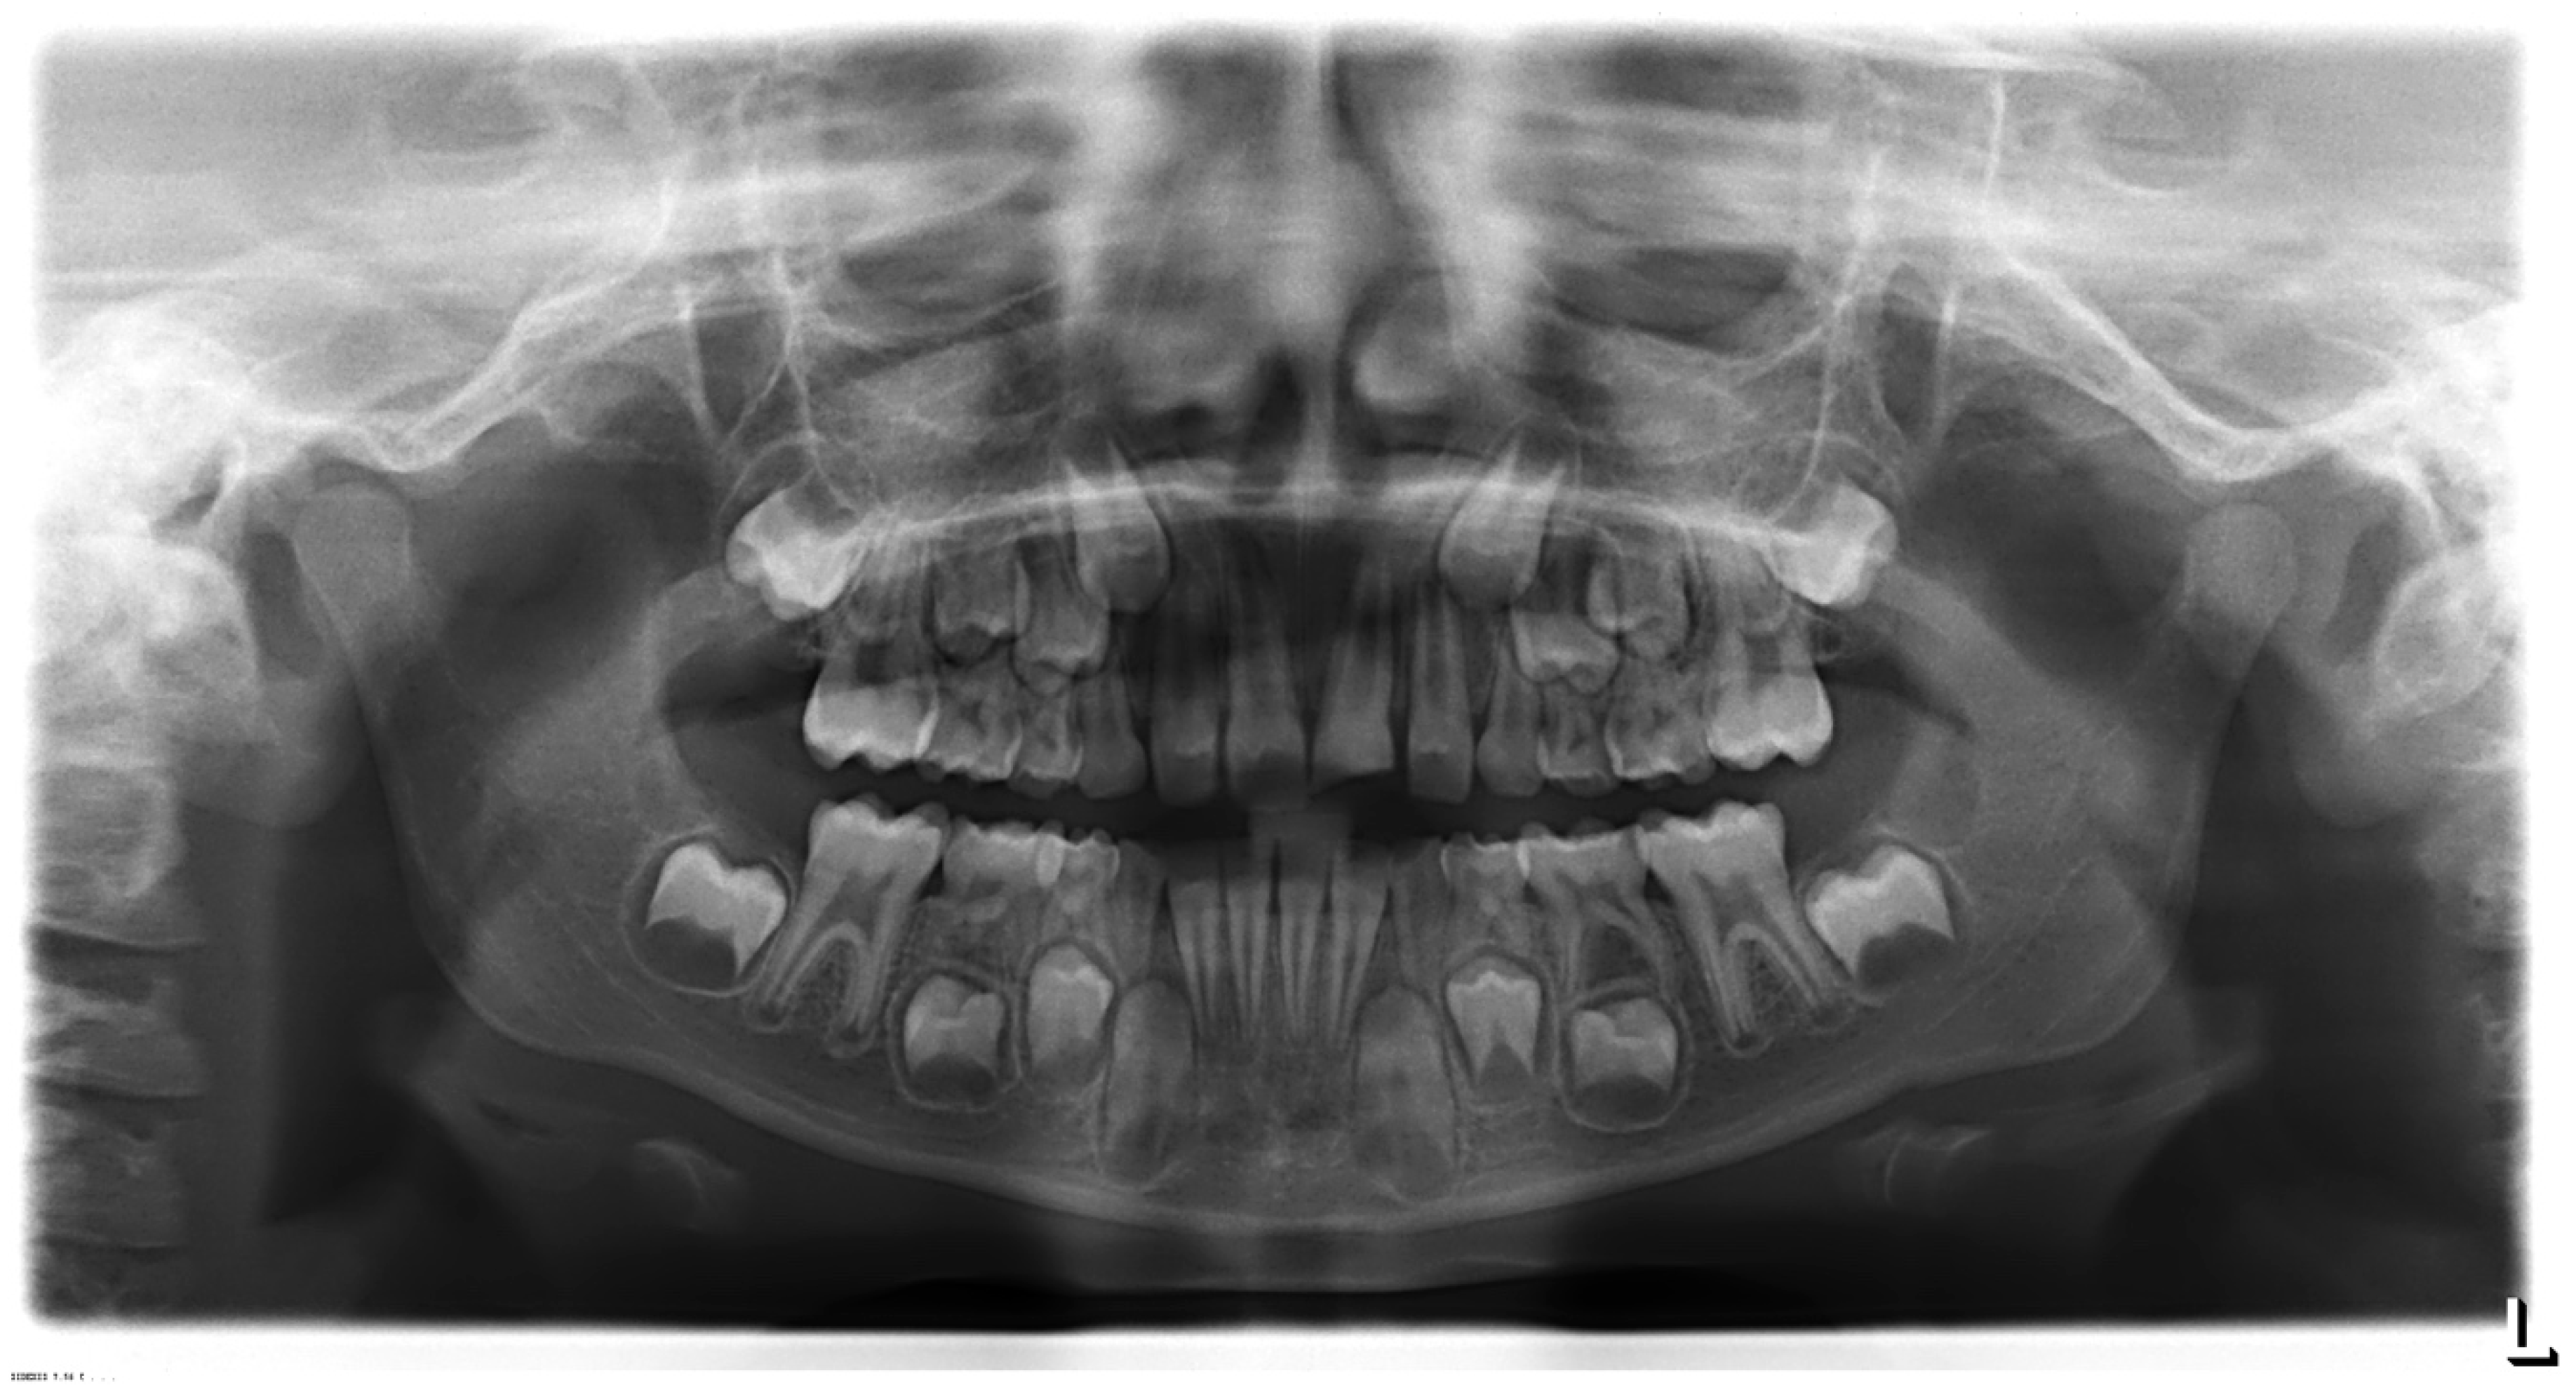

At the first visit, after the patient was anesthetized locally (2% lidocaine with 1:80,000 adrenaline) and the rubber dam placed, the restoration and the MTA were removed. Then, the root canal system was irrigated with 5.25% NaOCl and 17% liquid EDTA. The working length (18 mm) was electronically measured with a Root ZX (J. Morita) apex locator and the radiography confirmed. Later, the canals were dried using paper points and Ca(OH)2 (Ultracal, Ultradent, South Jordan, UT, USA) was placed into the canal. The access cavity was sealed with temporary restoration. At the second visit, three weeks later, the Ca(OH)2 was washed out by saline irrigation, and approximately 3 mm of MTA (ProRoot, Dentsply, Ballaigues, Switzerland) was placed from the root end (Figure 5C), and over the canal, an pulp chamber were obturated with gutta percha, system B&L (Figure 5D). Then, the access cavity was sealed and covered with a modified glass ionomer cement (GC Fugi II; GC Corporation, Japan). Finally, the endodontic access was restored with HRi/UD1 Enamel Plus (Micerium, Avegno, Italy), a high value color due to the typical MTA discoloration [,]. Furthermore, the veneer was polished to improve the esthetic appearance (Figure 6).

Figure 6.

Intra-oral photography. Clinical aspect of the lateral (A,B), buccal (C), and palatal (D) view after the 4-year follow-up.

This article reports an attempt to resolve an unsuccessful REP by the apexification with MTA. Next, we decided to apply an indirect composite veneer due to color stability []. This treatment option was effective until a 4-year follow-up, which allows a number of restorative management options to be considered in the future, if the esthetics is suddenly compromised.